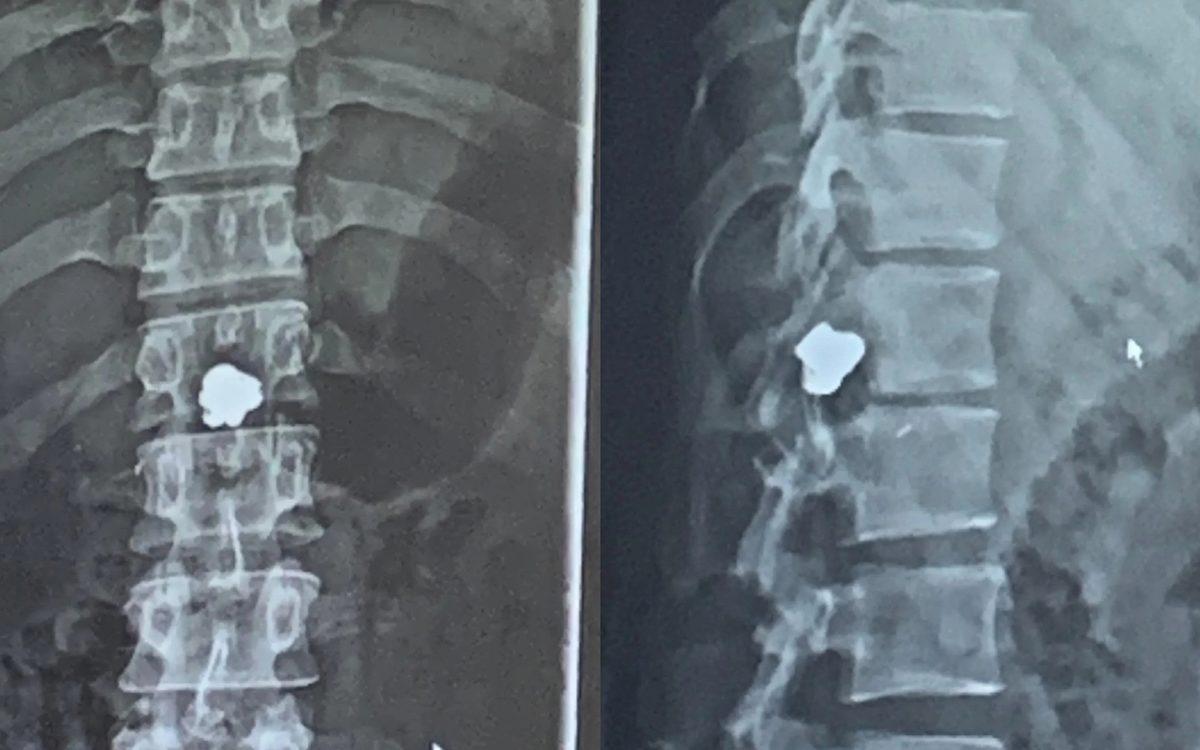

- Omurgasına kurşun isabet eden bir suçlu.

Bir hafta boyunca komada kalmasına neden olmuş.